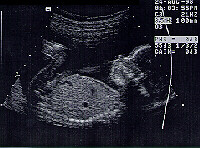

Josh's Face Front face view lying on his back with the head on the left. (The Skeletor Alien Look)